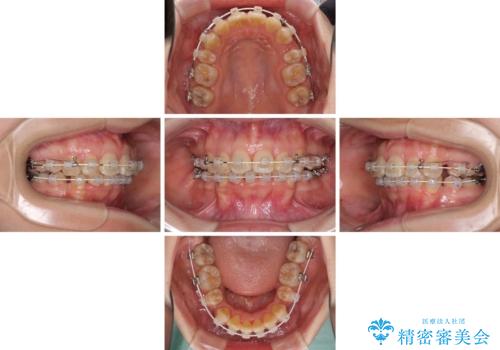

- 矯正装置

- 審美装置

- 口元の閉じにくさと、前歯のでこぼこの歯並びを気にして来院された患者様です。

口元を積極的に引っ込めるために、上下左右の小臼歯計4本を抜歯することとしました。

咬み合わせが深く、咬合力強いため、補助装置を使用しながら積極的に口元を下げることとしました。